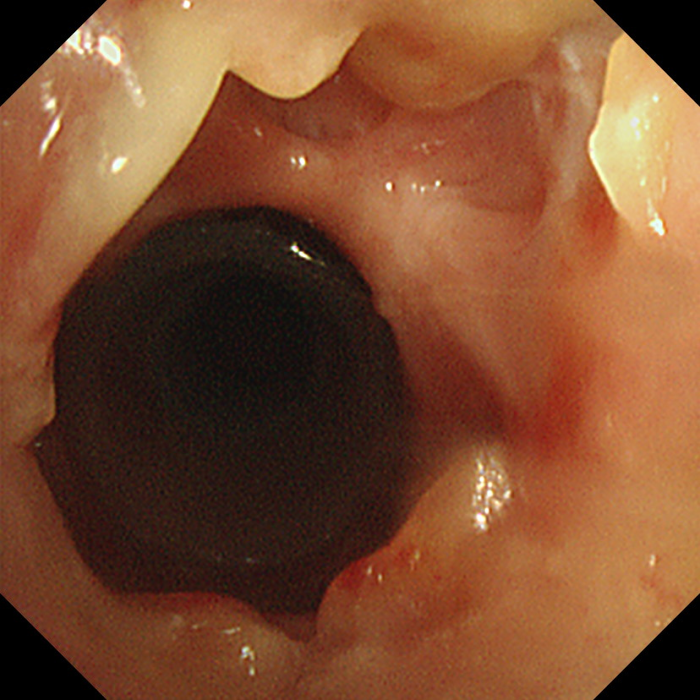

据了解,该患者为特殊瘢痕体质,因气管切开术后瘢痕过度生长,导致气管出现严重瘢痕增生与狭窄。此前,患者曾辗转多家医院,反复接受包括冷冻、电切、烧灼及气管支架置入在内的气管重塑术治疗,但效果均不理想,瘢痕仍反复增生,导致其呼吸受阻,生活质量受到严重影响。

患者气管出现严重瘢痕增生与狭窄

为寻求一线生机,患者在外院置入了硅酮支架并进行了缝合外固定。然而,由于术后反复剧烈咳嗽,外固定缝线不幸断裂,导致硅酮支架移位。移位的支架不仅未能解决狭窄问题,反而持续刺激气道,引发更剧烈的咳嗽并刺激瘢痕生长,形成恶性循环,使患者病情一度陷入困境。